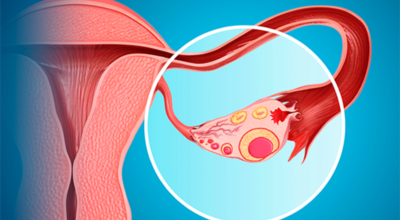

난소낭종이란 난소에 발생되는 물혹이지요. 안에는 그냥 수액이나 장액이지만, 혈액일 수도 있으며, 지방이나 농양일 수도 있어요. 이 난소낭종은 없어졌다 생겼다 하는 기능성 낭종과 점점 커지는 악성 낭종으로 나뉘는데요. 주로 악성 낭종이 문제일 것이라고 생각하지만 기능성 낭종도 커지면 터지면서 사람을 응급실로 실려가게 만들어요.

기능성 낭종 : 배란 낭종이라고도 하며 보통은 증상을 유발하지 않는 가장 흔한 종류의 낭종이지요. 그들은 난포 낭종 ( 난포에서 발생, 난소의 작은 주머니) 및 황체 낭포(난포가 난자를 방출한 후 발생)로 형성될 수 있어요.

유피종 및 기형종 : 태어날 때 부터 존재하며 머리카락, 뼈, 치아 및 피부와 같은 다른 조직을 포함합니다. 여성의 십만 명에 열명 정도가 이러한 유형의 낭종이 있는 것으로 추정되는 비교적 드문 경우이지요 .

낭종: 난소 표면에 형성되며 난소의 체액이나 일부 조직으로 채워져 있어요.

자궁내막증 : 이것은 자궁 외부 조직에서 자자고 혈액으로 가득 찬 낭종이지요.